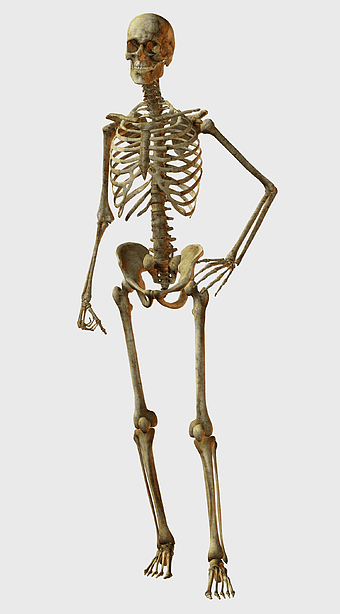

human skeleton illustration, human anatomy bones, skeletal system diagram, human body structure, anatomical reference, medical illustration, educational skeleton image -

Human skeleton, human body anatomy, standing skeleton, bone structure, skeletal system, medical illustration, human anatomy study -

human skeleton, bone structure, nervous system anatomy, joint function, skeletal framework, anatomical illustration, human body composition -

human skeleton illustration, white skeleton decor, rib cage anatomy, vertebral column drawing, skeletal system diagram, medical skeleton art, human bones structure -